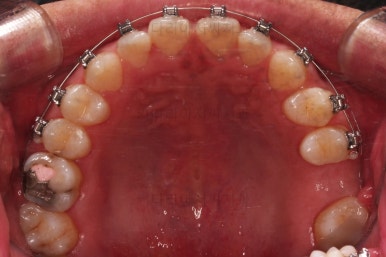

초진 시의 입안 모습입니다.

어금니가 빠져서 결손치아가 있고 치아 사이에 틈새도 있어서 교정치료도 함께 원한다고 내원해 주셨어요.

사진에서 보시는 바와 같이 윗니 1개, 아랫니 1개의 결손 부위가 보입니다.

윗니 어금니 중에는 신경치료를 마무리 못하고 임시재료로 메꿔뒀던 부위도 보이고요.

틈새는 서서히 조여서 없애주고요.

임플란트를 하기에 적절한 사이즈로 공간은 맞춰줍니다.